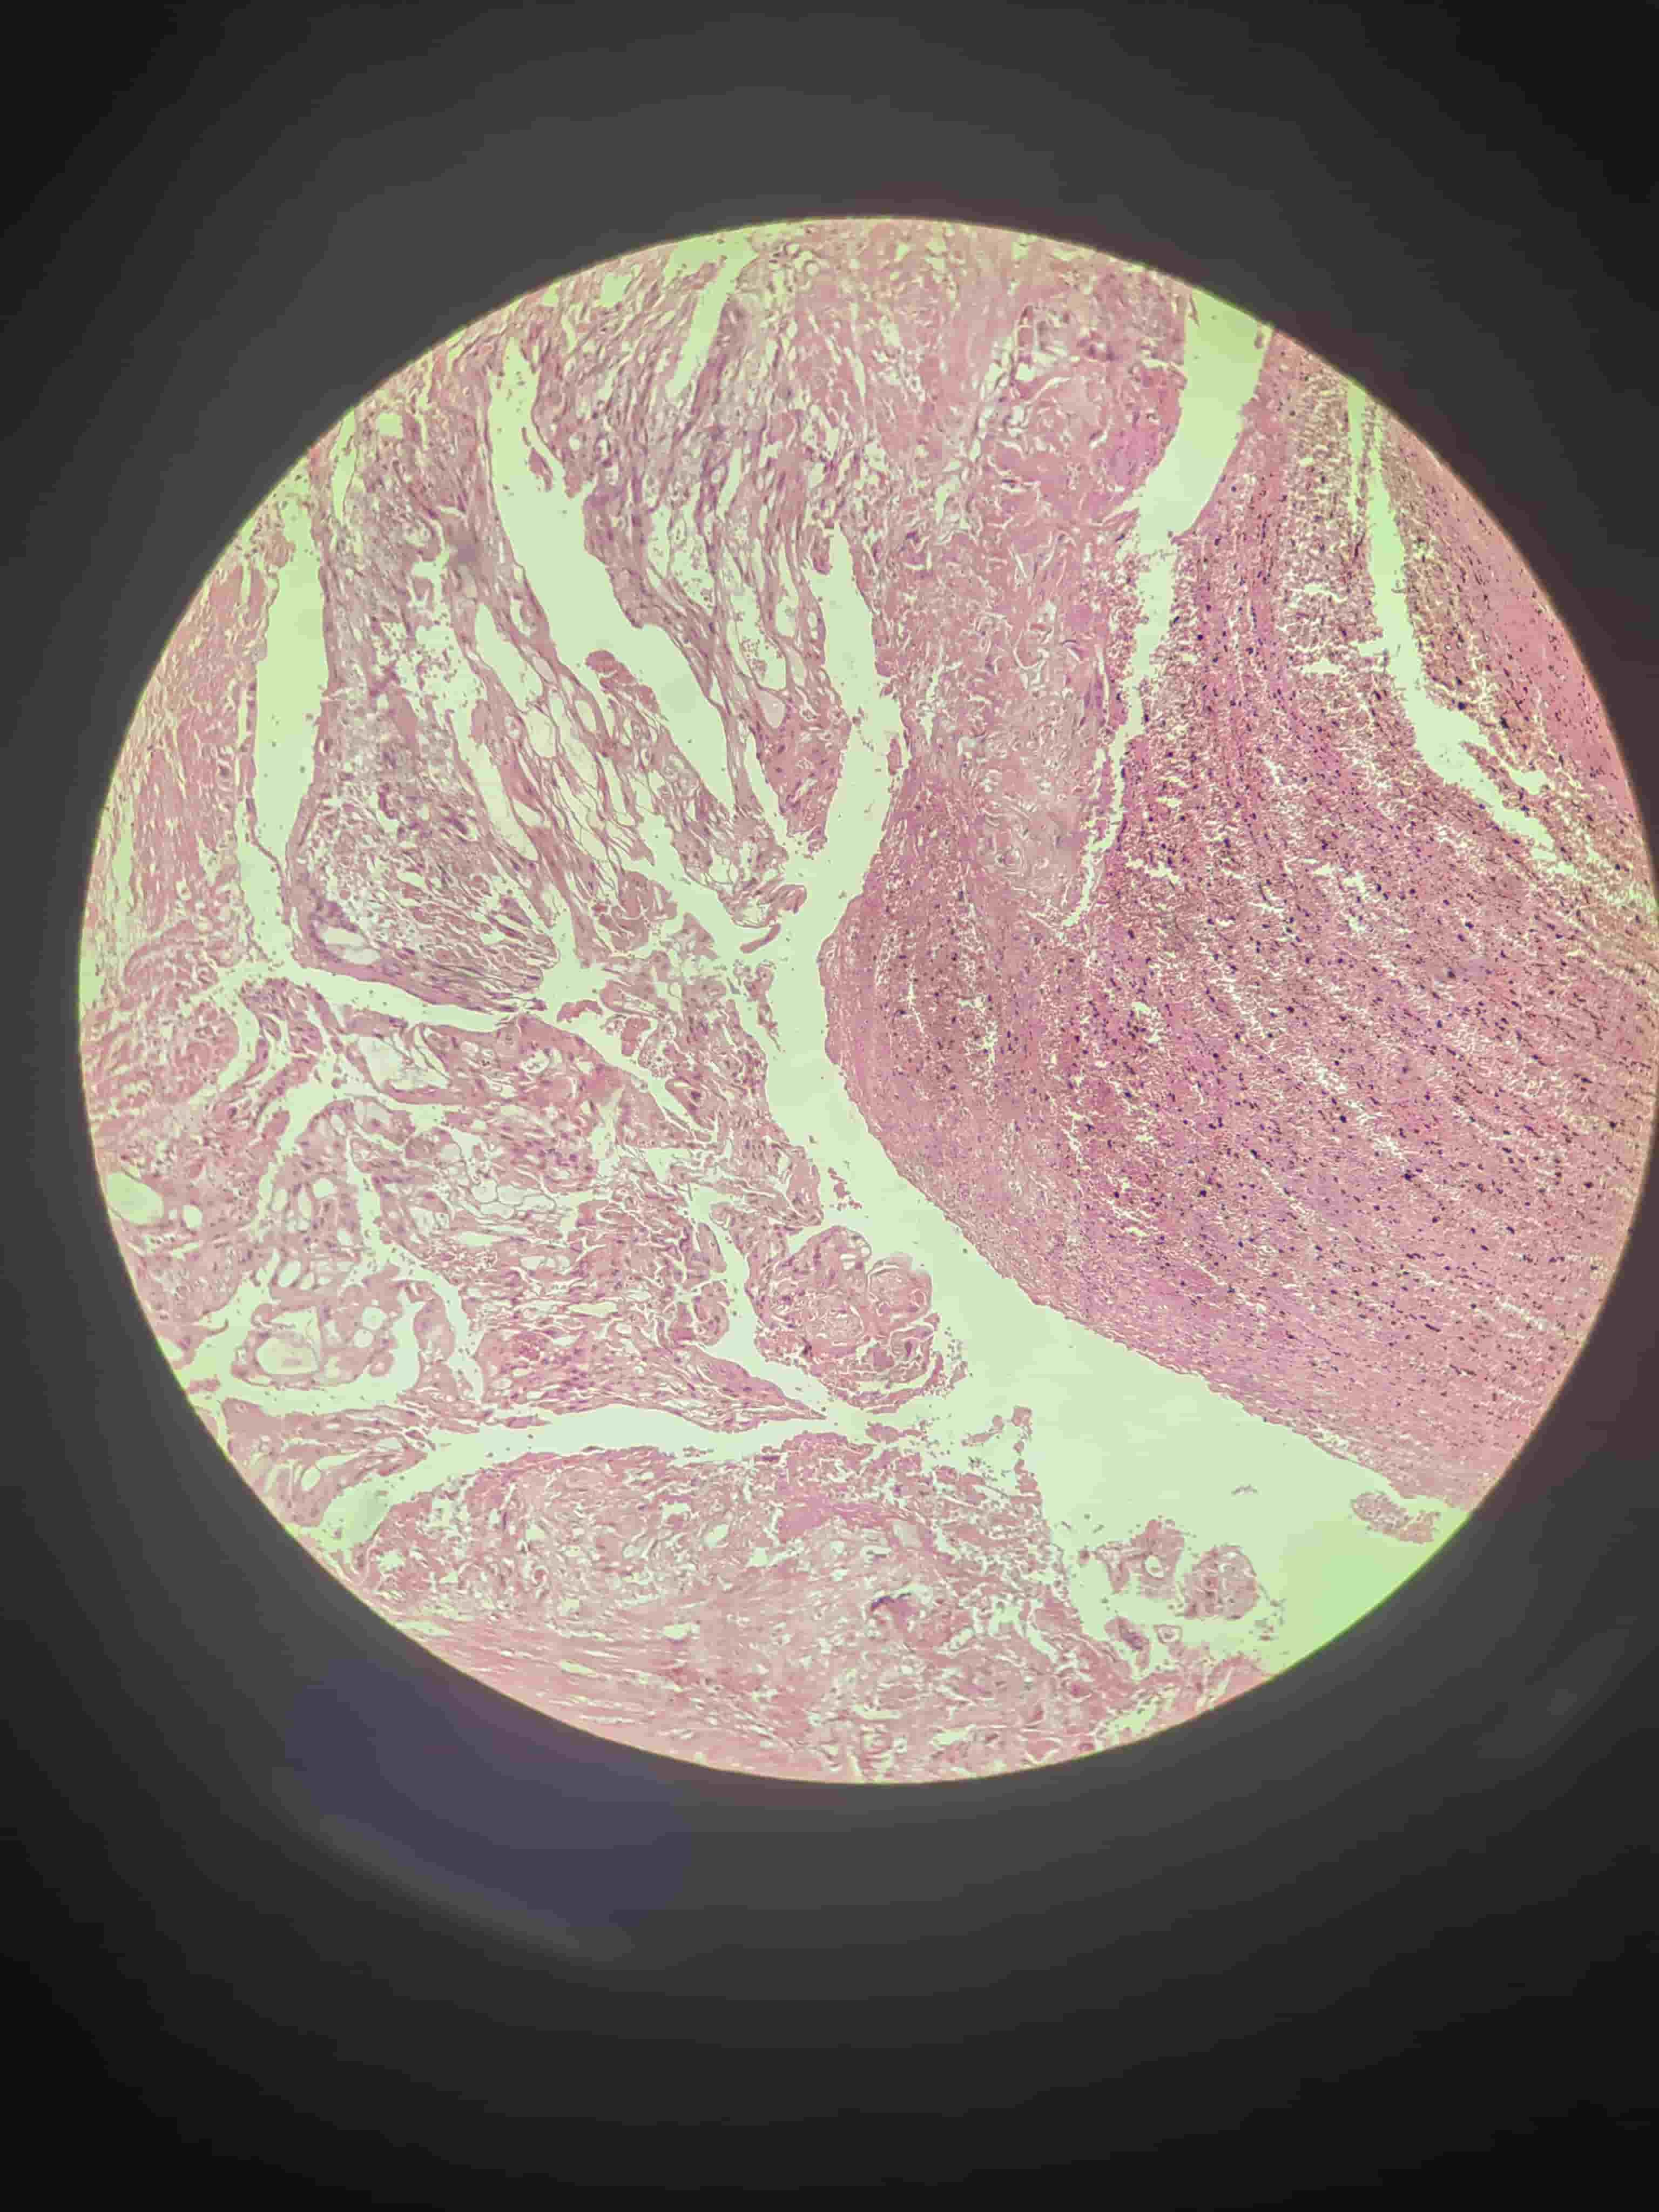

慢性胃溃疡